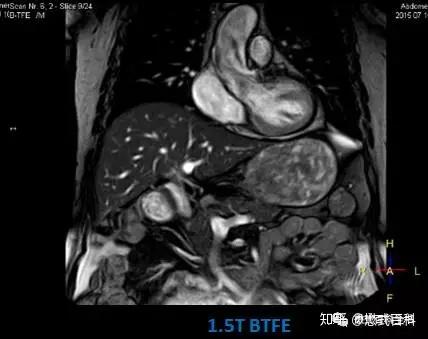

3 0t和1 5t磁共振扫描序列有哪些不同 知乎

1 5t与3t核磁共振 Mri 知乎

临床医生应该知道的磁共振知识 如何判断磁共振图像 知乎